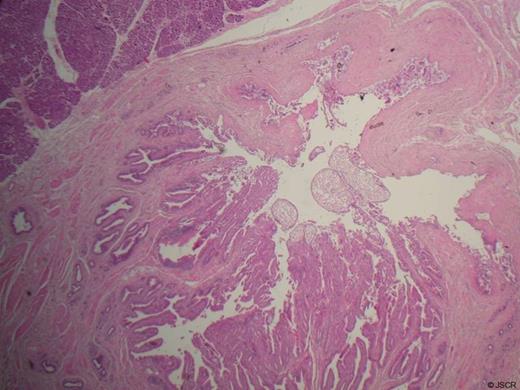

The histology of the resected specimen was reported as showing intramural benign gland hyperplasia within the distal CBD and ampulla (Figure 5).

Histology at x100 magnification demonstrating glandular lobules of duct-like structures within fibrous stroma of the ampulla